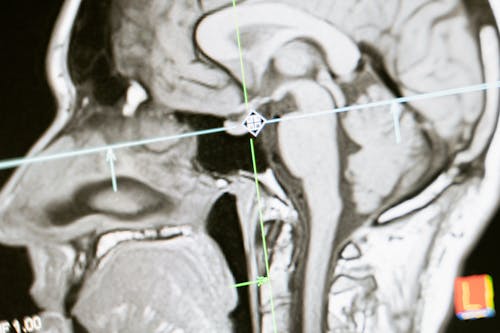

모야모야병 진단, 어떻게 할까? MRI·MRA가 핵심

모야모야병이 의심된다면 신경과 전문의와 상담해야 합니다. 주요 검사 방법은 다음과 같습니다.

- MRI & MRA (뇌혈관 영상)

- 뇌혈관의 좁아진 부분과 모야모야 혈관(연기 모양) 확인